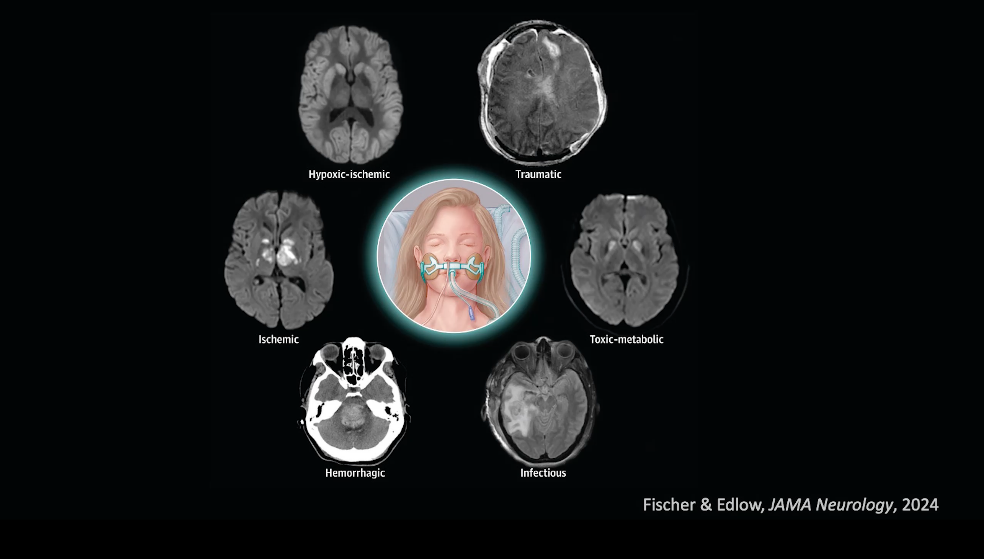

Dr. Fischer describes a framework for reasoning through neuroprognostication in disorders of consciousness, reviewing key principles and the state of the field in prognostic testing.